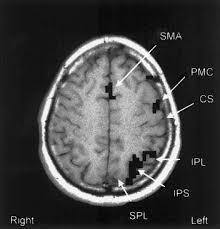

Agraphia An Overview Sciencedirect Topics